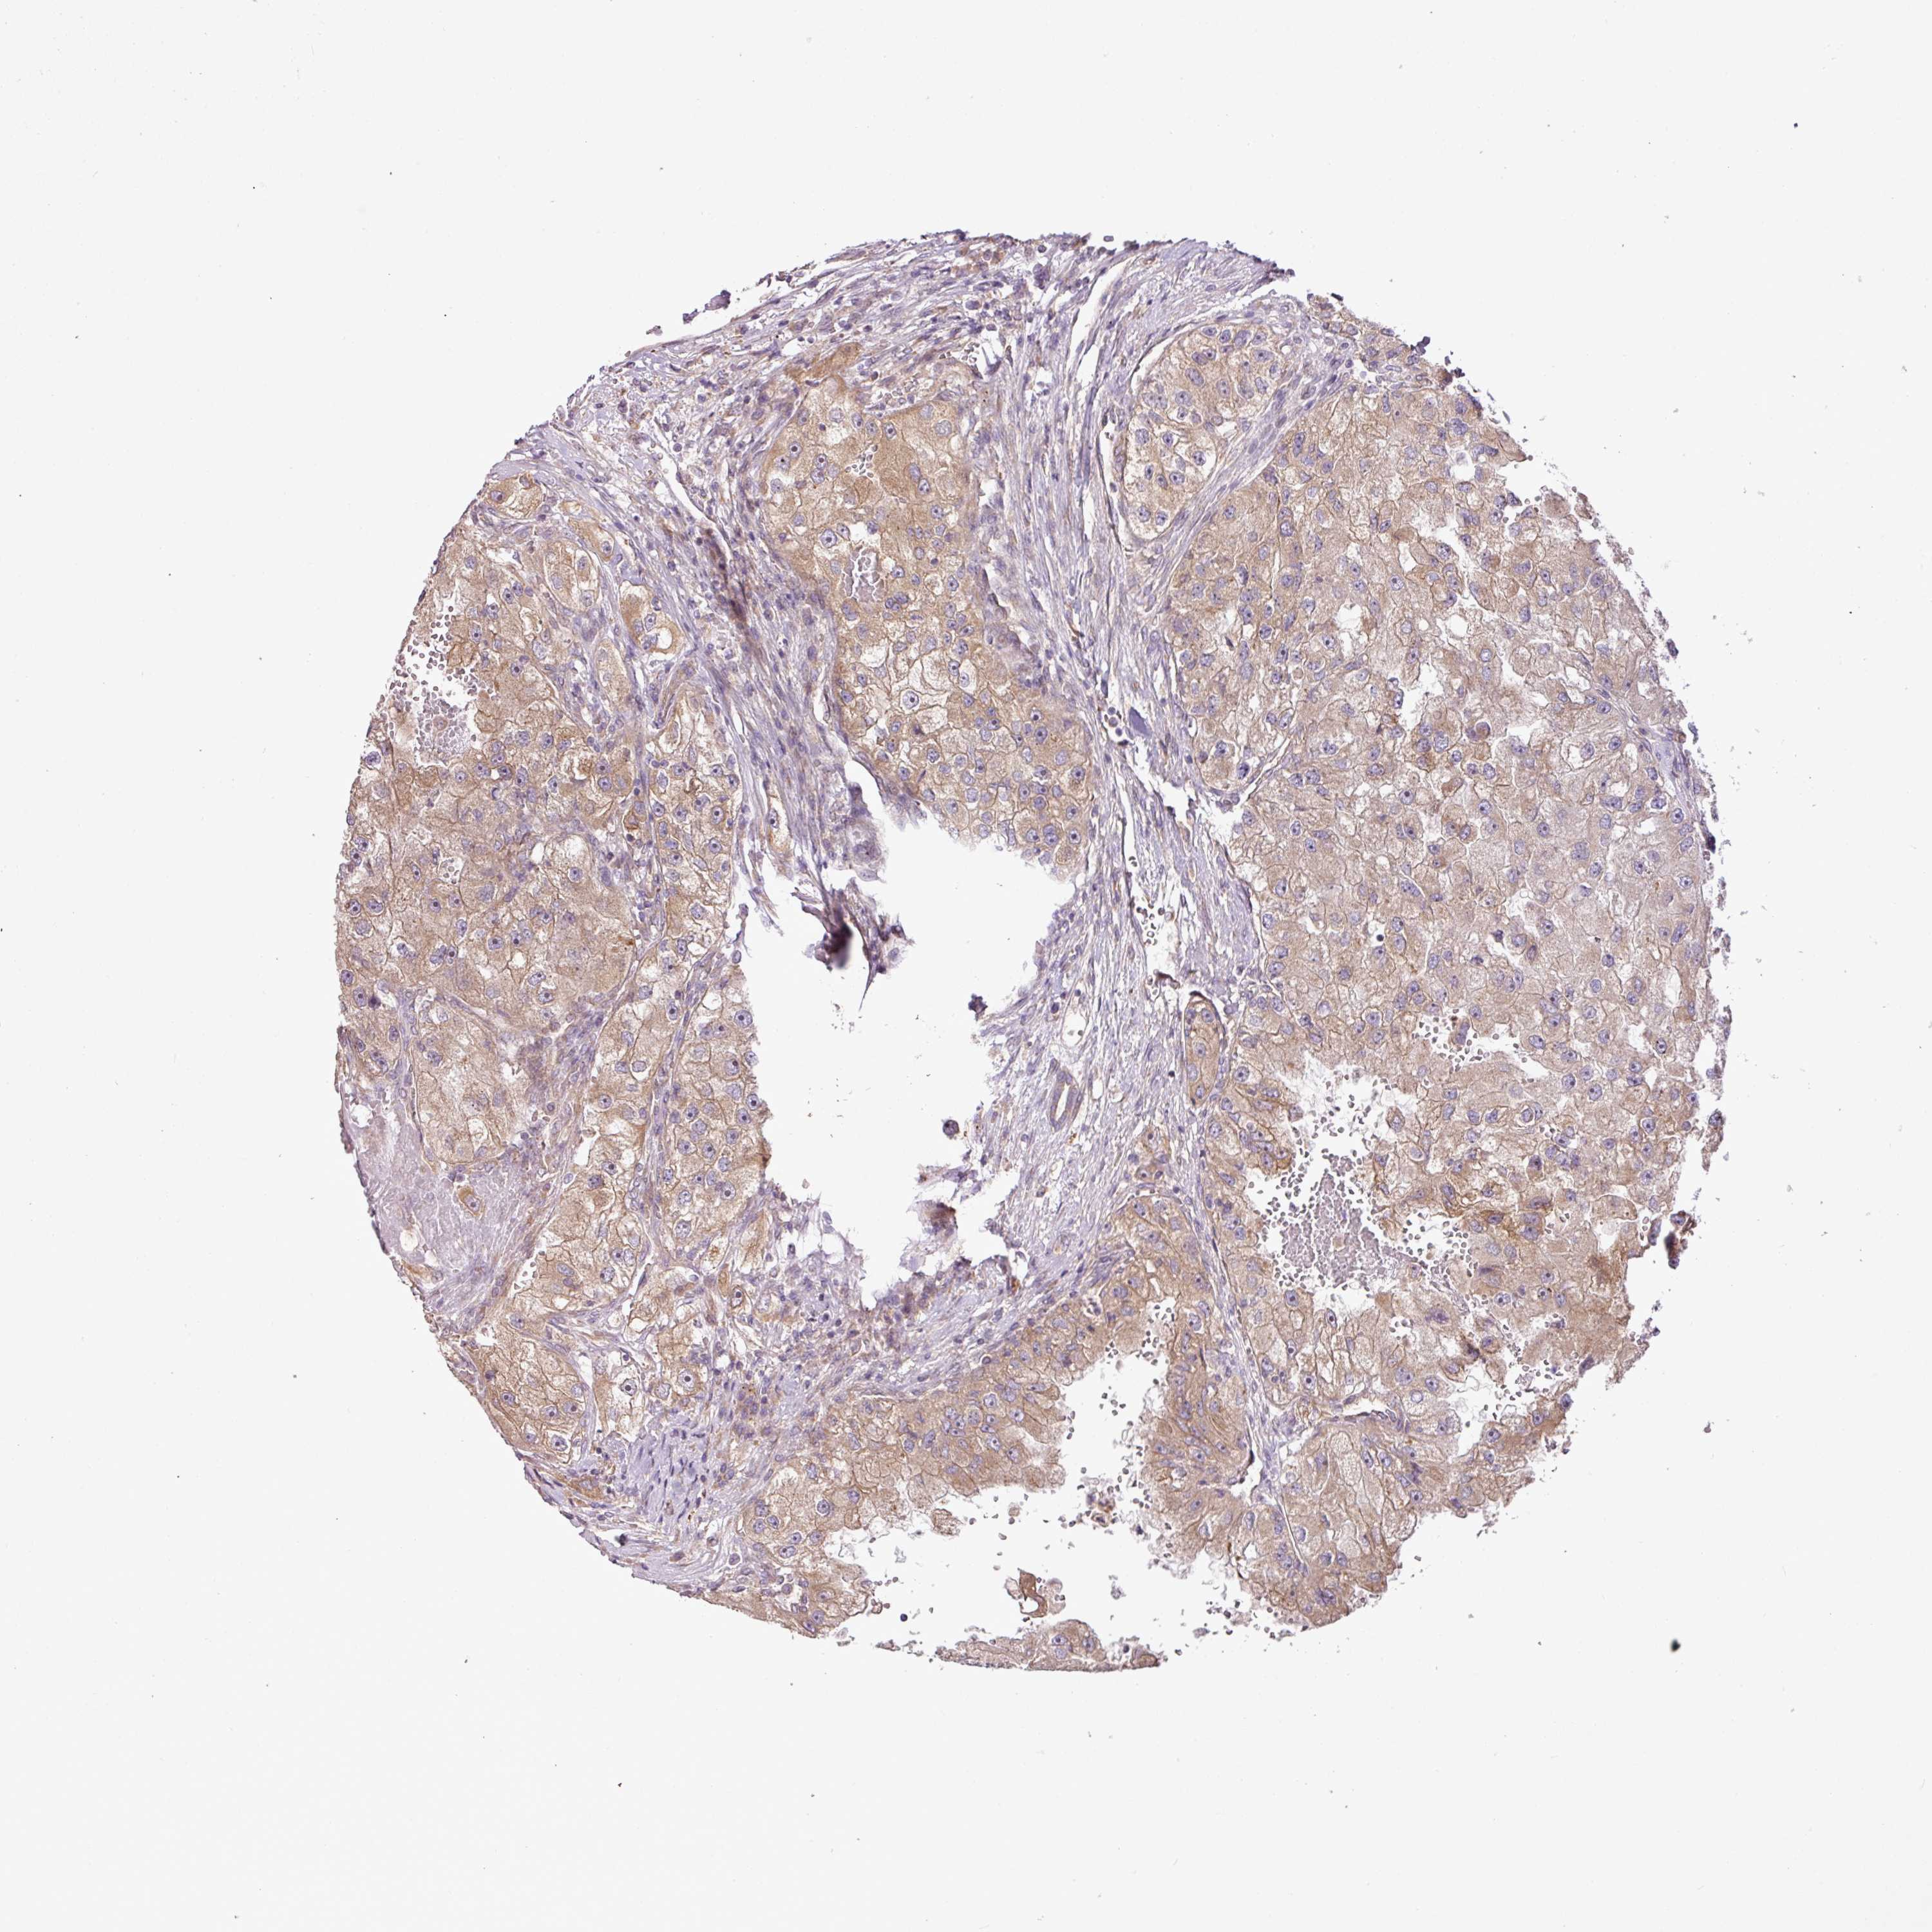

KIDNEY RENAL PAPILLARY CELL CARCINOMA (TCGA) - Interactive survival scatter ploti

The Survival Scatter plot shows the clinical status (i.e. dead or alive) for all individuals in the patient cohort, based on the same data that underlies the corresponding Kaplan-Meier plots. Patients that are alive at last time for follow-up are shown in blue and patients who have died during the study are shown in red.

The x-axis shows the expression levels (FPKM) of the investigated gene in the tumor tissue at the time of diagnosis. The y-axis shows the follow-up time after diagnosis (years). Both axes are complimented with kernel density curves demonstrating the data density over the axes. The top density plot shows the expression levels (FPKM) distribution among dead (red) and alive patients (blue). The right density plot shows the data density of the survived years of dead patients with high and low expression levels respectively, stratified using the cutoff indicated by the vertical dashed line through the Survival Scatter plot. This cutoff is automatically defined based on the FPKM cutoff that minimizes the p-score. The cutoff can be changed by dragging the vertical line or by entering a cutoff value in the square labeled "Current cut-off".

Under the Survival Scatter plot the p-score landscape (black curve; left axis) is shown together with dead median separation (red curve; right axis). Dead median separation is the difference in median mRNA expression between patients who have died with high and low expression, respectively. It is calculated as follows: median FPKM expression of dead patients with high expression - median FPKM expression of dead patients with low expression. This is intended to aid the user in visually exploring custom cutoffs and the associated p-scores and dead median separation.

Individual patient data is displayed and can be filtered by clicking on one or more of the category buttons on the top of the page. Categories describing expression level and patient information include: high, low, alive, dead, female, male and tumor stages. The scale of the x-axis can be toggled between linear and log-scale by clicking on the "x log" button. Mouse-over function shows TCGA ID, patient information and mRNA expression (FPKM) for each patient.

& Survival analysisi

Kaplan-Meier plots summarize results from analysis of correlation between mRNA expression level and patient survival. Patients were divided based on level of expression into one of the two groups "low" (under cut off) or "high" (over cut off). X-axis shows time for survival (years) and y-axis shows the probability of survival, where 1.0 corresponds to 100 percent.

COX18 is not prognostic in Kidney Renal Papillary Cell Carcinoma (TCGA)